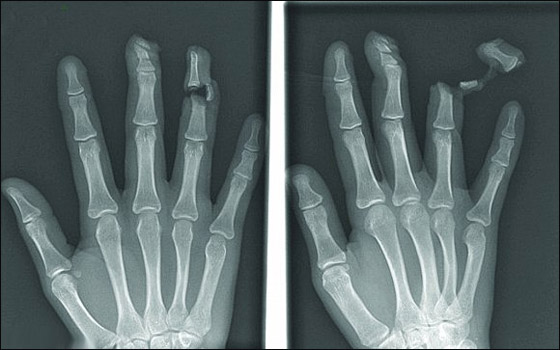

غير أن صورا أخرى مثل صورة الإصبع المقطوع أو المسمار الذي يخترق إصبعا مرعبة أكثر مما هي طريفة.

اصبع مكسور